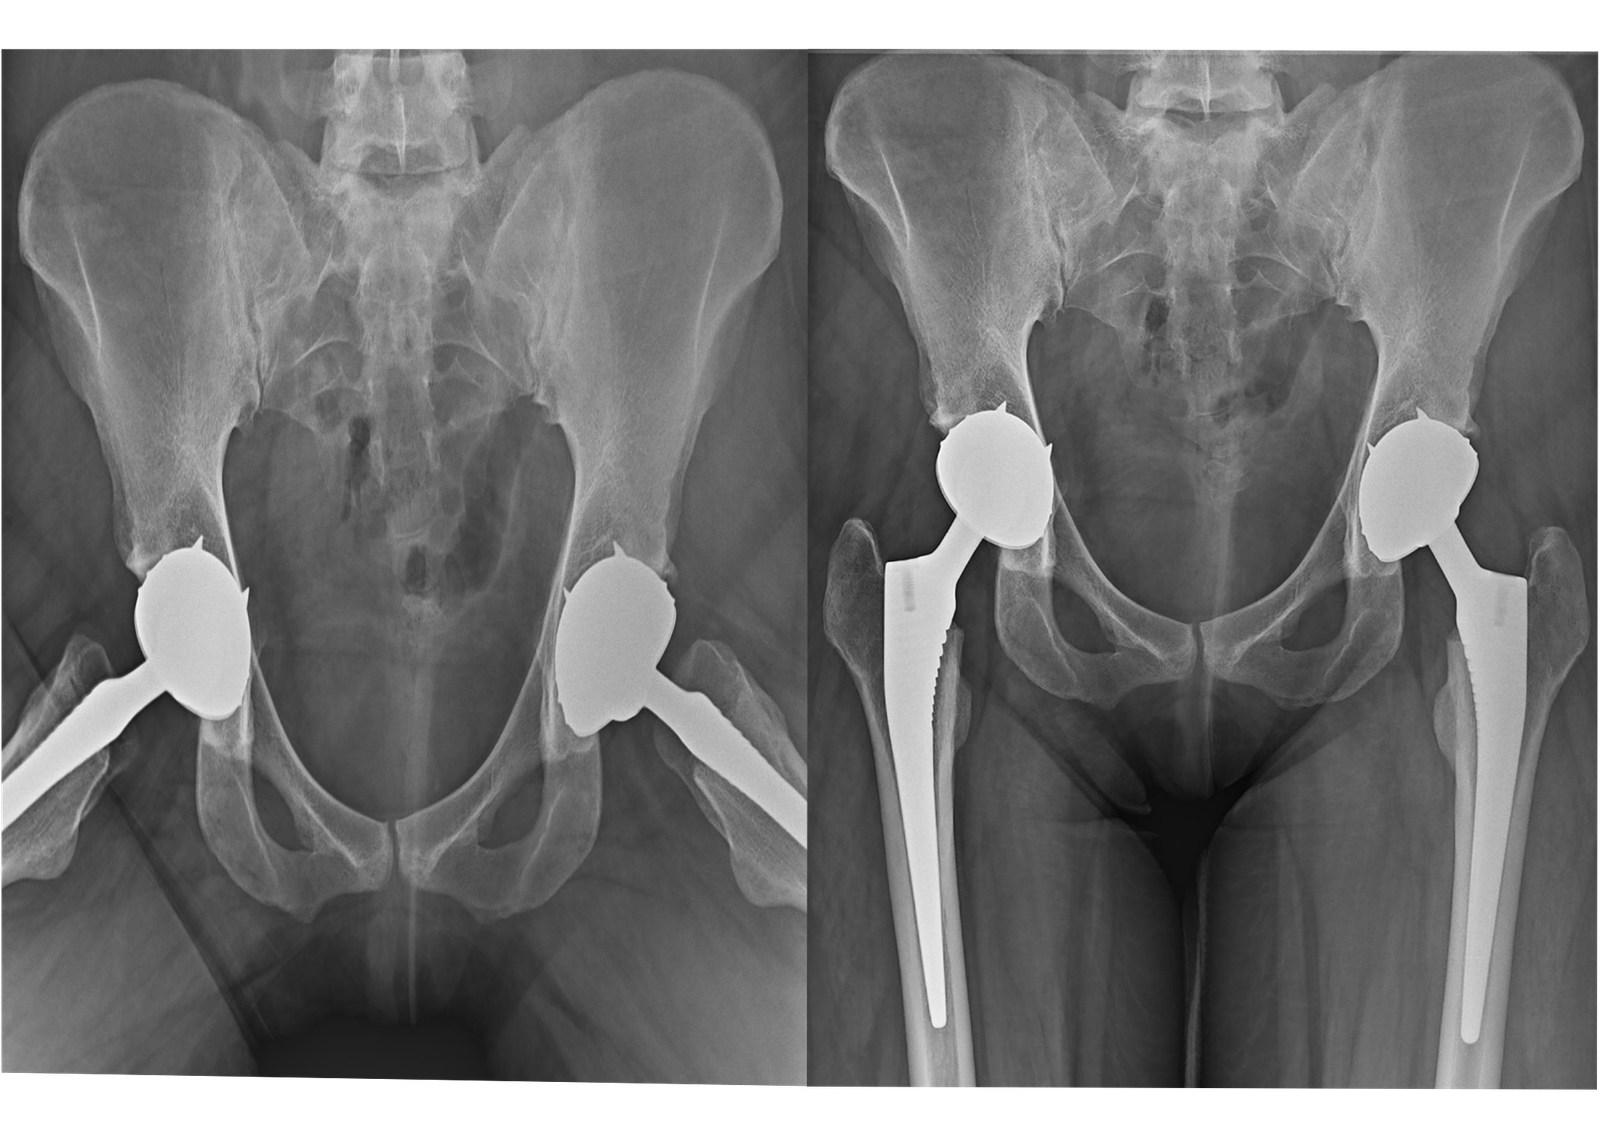

2. Total Hip Replacement (THR):

For patients experiencing debilitating hip pain due to arthritis, fractures, or other conditions, our Total Hip Replacement services offer a reliable solution. Our surgeons utilize minimally invasive techniques to reduce recovery time and improve surgical outcomes, ensuring that patients can return to their daily activities with greater ease.